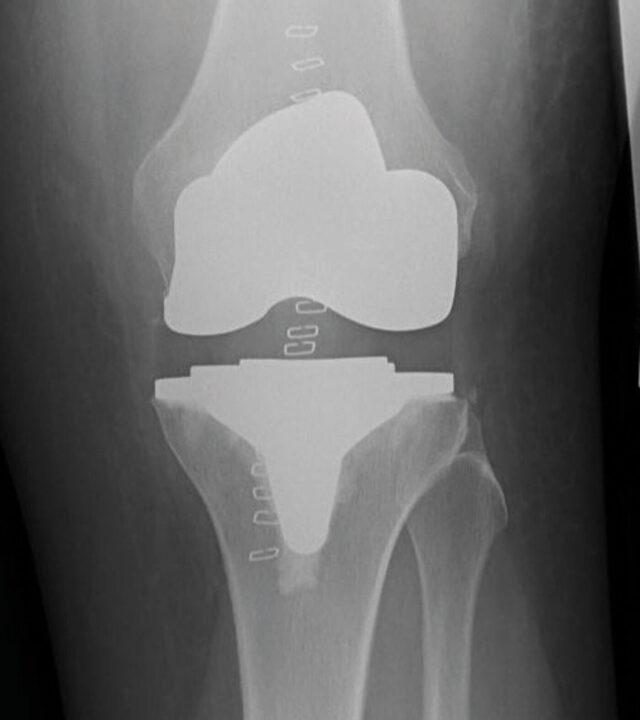

Röntgenaufnahmen einer 70-jährigen Patientin mit langjähriger chronischer Arthritis: Die ausgeprägte O-Bein-Stellung mit 30° Varus-Deformität zeigt die fortgeschrittene Gelenkzerstörung. Eine Korrektur und Begradigung war nur durch den Einsatz einer gekoppelten Scharnierendoprothese möglich. (Vorher-Nachher-Vergleich).